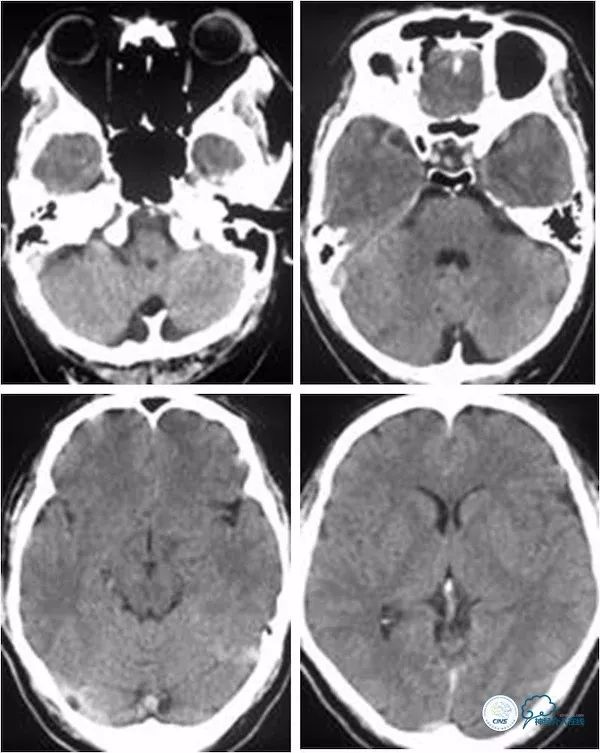

患者,男,49岁。主因“头晕、视物重影17天”入院。17天前患者无明显诱因突然出现头晕、视物重影,伴行走欠稳,就诊当地医院,行头颅CT平扫未见明显异常(图1)。

图1

头颅核磁检查:未见明显新近梗死(图2)。

图2